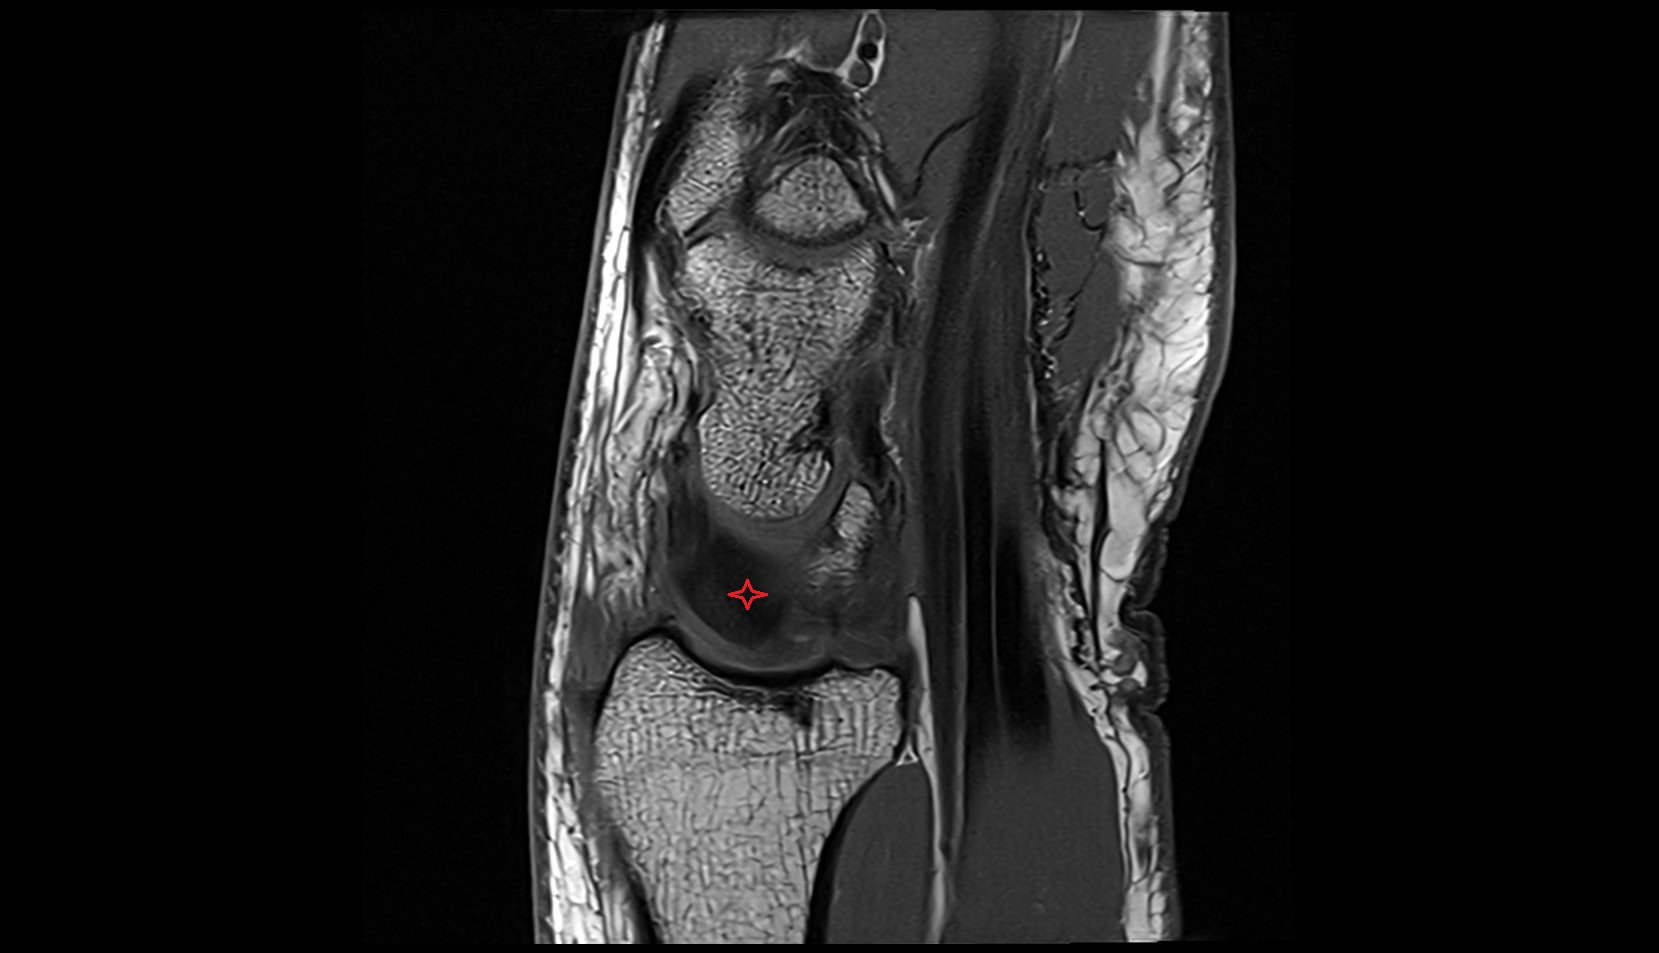

- Medial meniscus

- Lateral meniscus

- Knee Joint